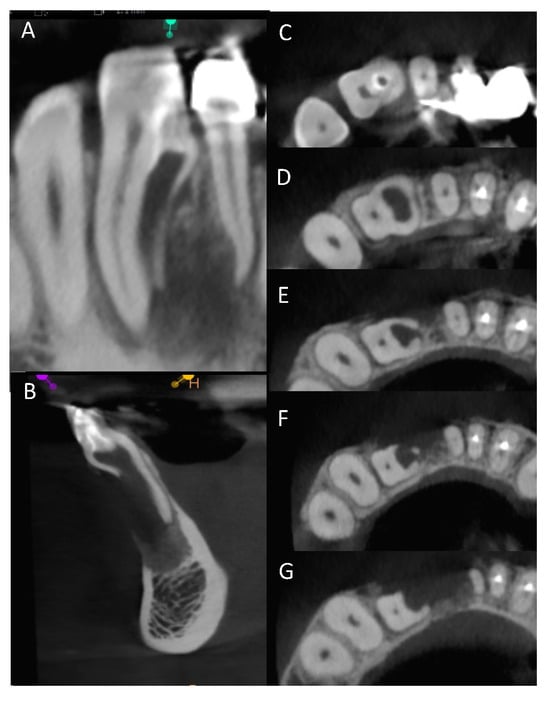

- The comparison between the use of 3D printing and milling with the use of Materialise software, as used in the current study, was profiled in a study by Kachhara et al. They concluded that an exact tooth replica can be created to assist in treatment planning [26]. The ability of the clinician to view a 3D model versus manipulating a CBCT image in the axial, sagittal, and coronal views, is beneficial to appreciating the fine detail of the unique root anatomy. The exact replica is produced to a high level of detail that can be directly viewed. Being able to handle the physical model provides an opportunity to manipulate and observe the model and appreciate the unique characteristics of the tooth and root anatomy when conceptualizing the proposed nonsurgical and surgical endodontic treatment.